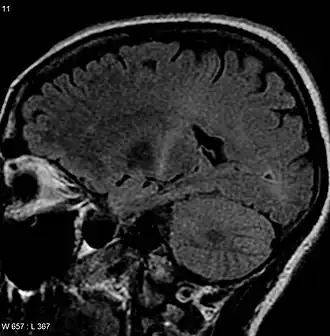

- МРТ головного и спинного мозга

- выявление отмирания пирамидных путей на МРТ